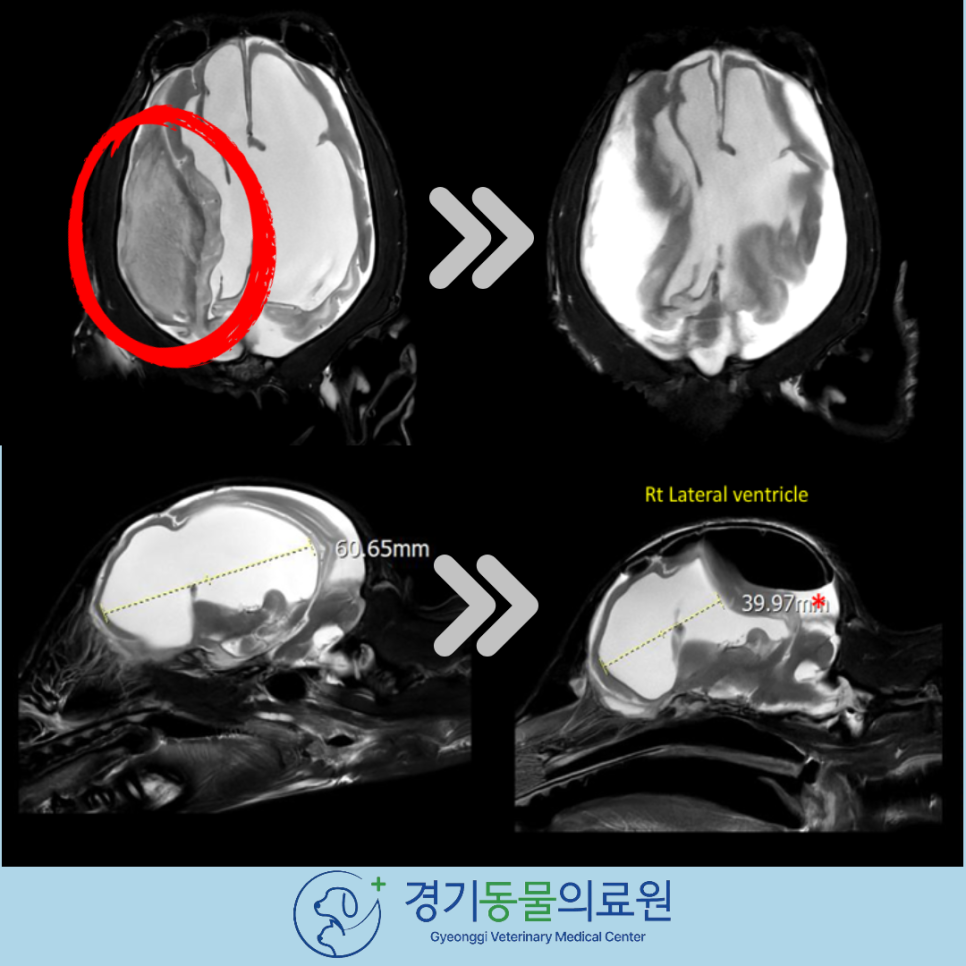

강아지 MRI 촬영 결과, 검사 화면에서 강아지 뇌 내 병변을 확인할 수 있었습니다.

MRI 상에서 다양한 시퀀스를 종합하여 볼 때 뇌내혈종(hematoma) 가능성이높게고려되었습니다.

강아지 뇌내혈종으로 인해 뇌척수액의 흐름이 원활하지 못해 뇌수두증이 동반된 상태였습니다.

성공적으로 제거된 강아지 뇌 혈종입니다. 수술 후 MRI 상에서 혈종이 제거된 것을 확인하였고, 확장되었던 뇌실 또한 줄어들었습니다.

뇌척수액의 흐름을 방해하던 혈종을 제거해 주었기 때문에, 막혔던 뇌척수액의 흐름또한 개선될 것입니다.